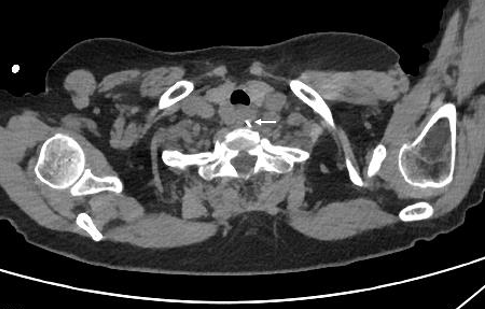

不料次日醒来,张奶奶感觉喉咙痛得更厉害了。家人赶紧带她到当地医院就诊,食道CT提示,食道上段有一长约1.5厘米的异物,同时食管穿孔。但随后食道镜检查,却怎么也找不到鱼刺。鱼刺究竟去哪儿了?医生建议立即转往武汉大学人民医院(湖北省人民医院)东院区。

该院耳鼻咽喉头颈外I科主任朱霆教授接诊后仔细查看了CT影像,认为异物极有可能已穿透食道并游走到了颈部。此时张奶奶已经5天无法经口进食,仅靠输液维持生命体征,颈深部间隙可能已出现感染。若再不找到并立即取出异物,颈深部感染及纵隔感染几乎无法避免,后果不堪设想。